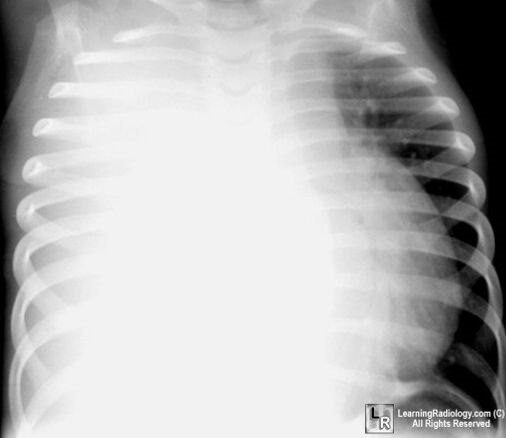

Pictorial Differential Diagnoses

Click on the tabs to see the differential; click on the photo to enlarge;

click on the text beneath the photo for more information

Pulmonary Differentials